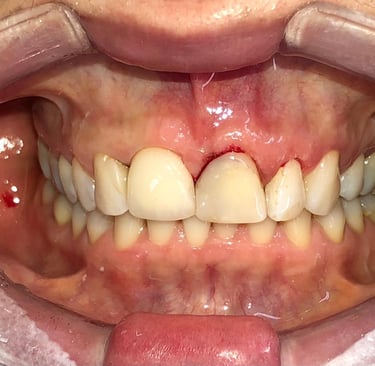

Cirurgia de aumento de coroa clínica antes das coroas

Caso que demonstra a vantagem da integração de diversas áreas da odontologia, unindo cirurgia, periodontia, prótese e estética para alcançar resultados funcionais e harmônicos.

Depois